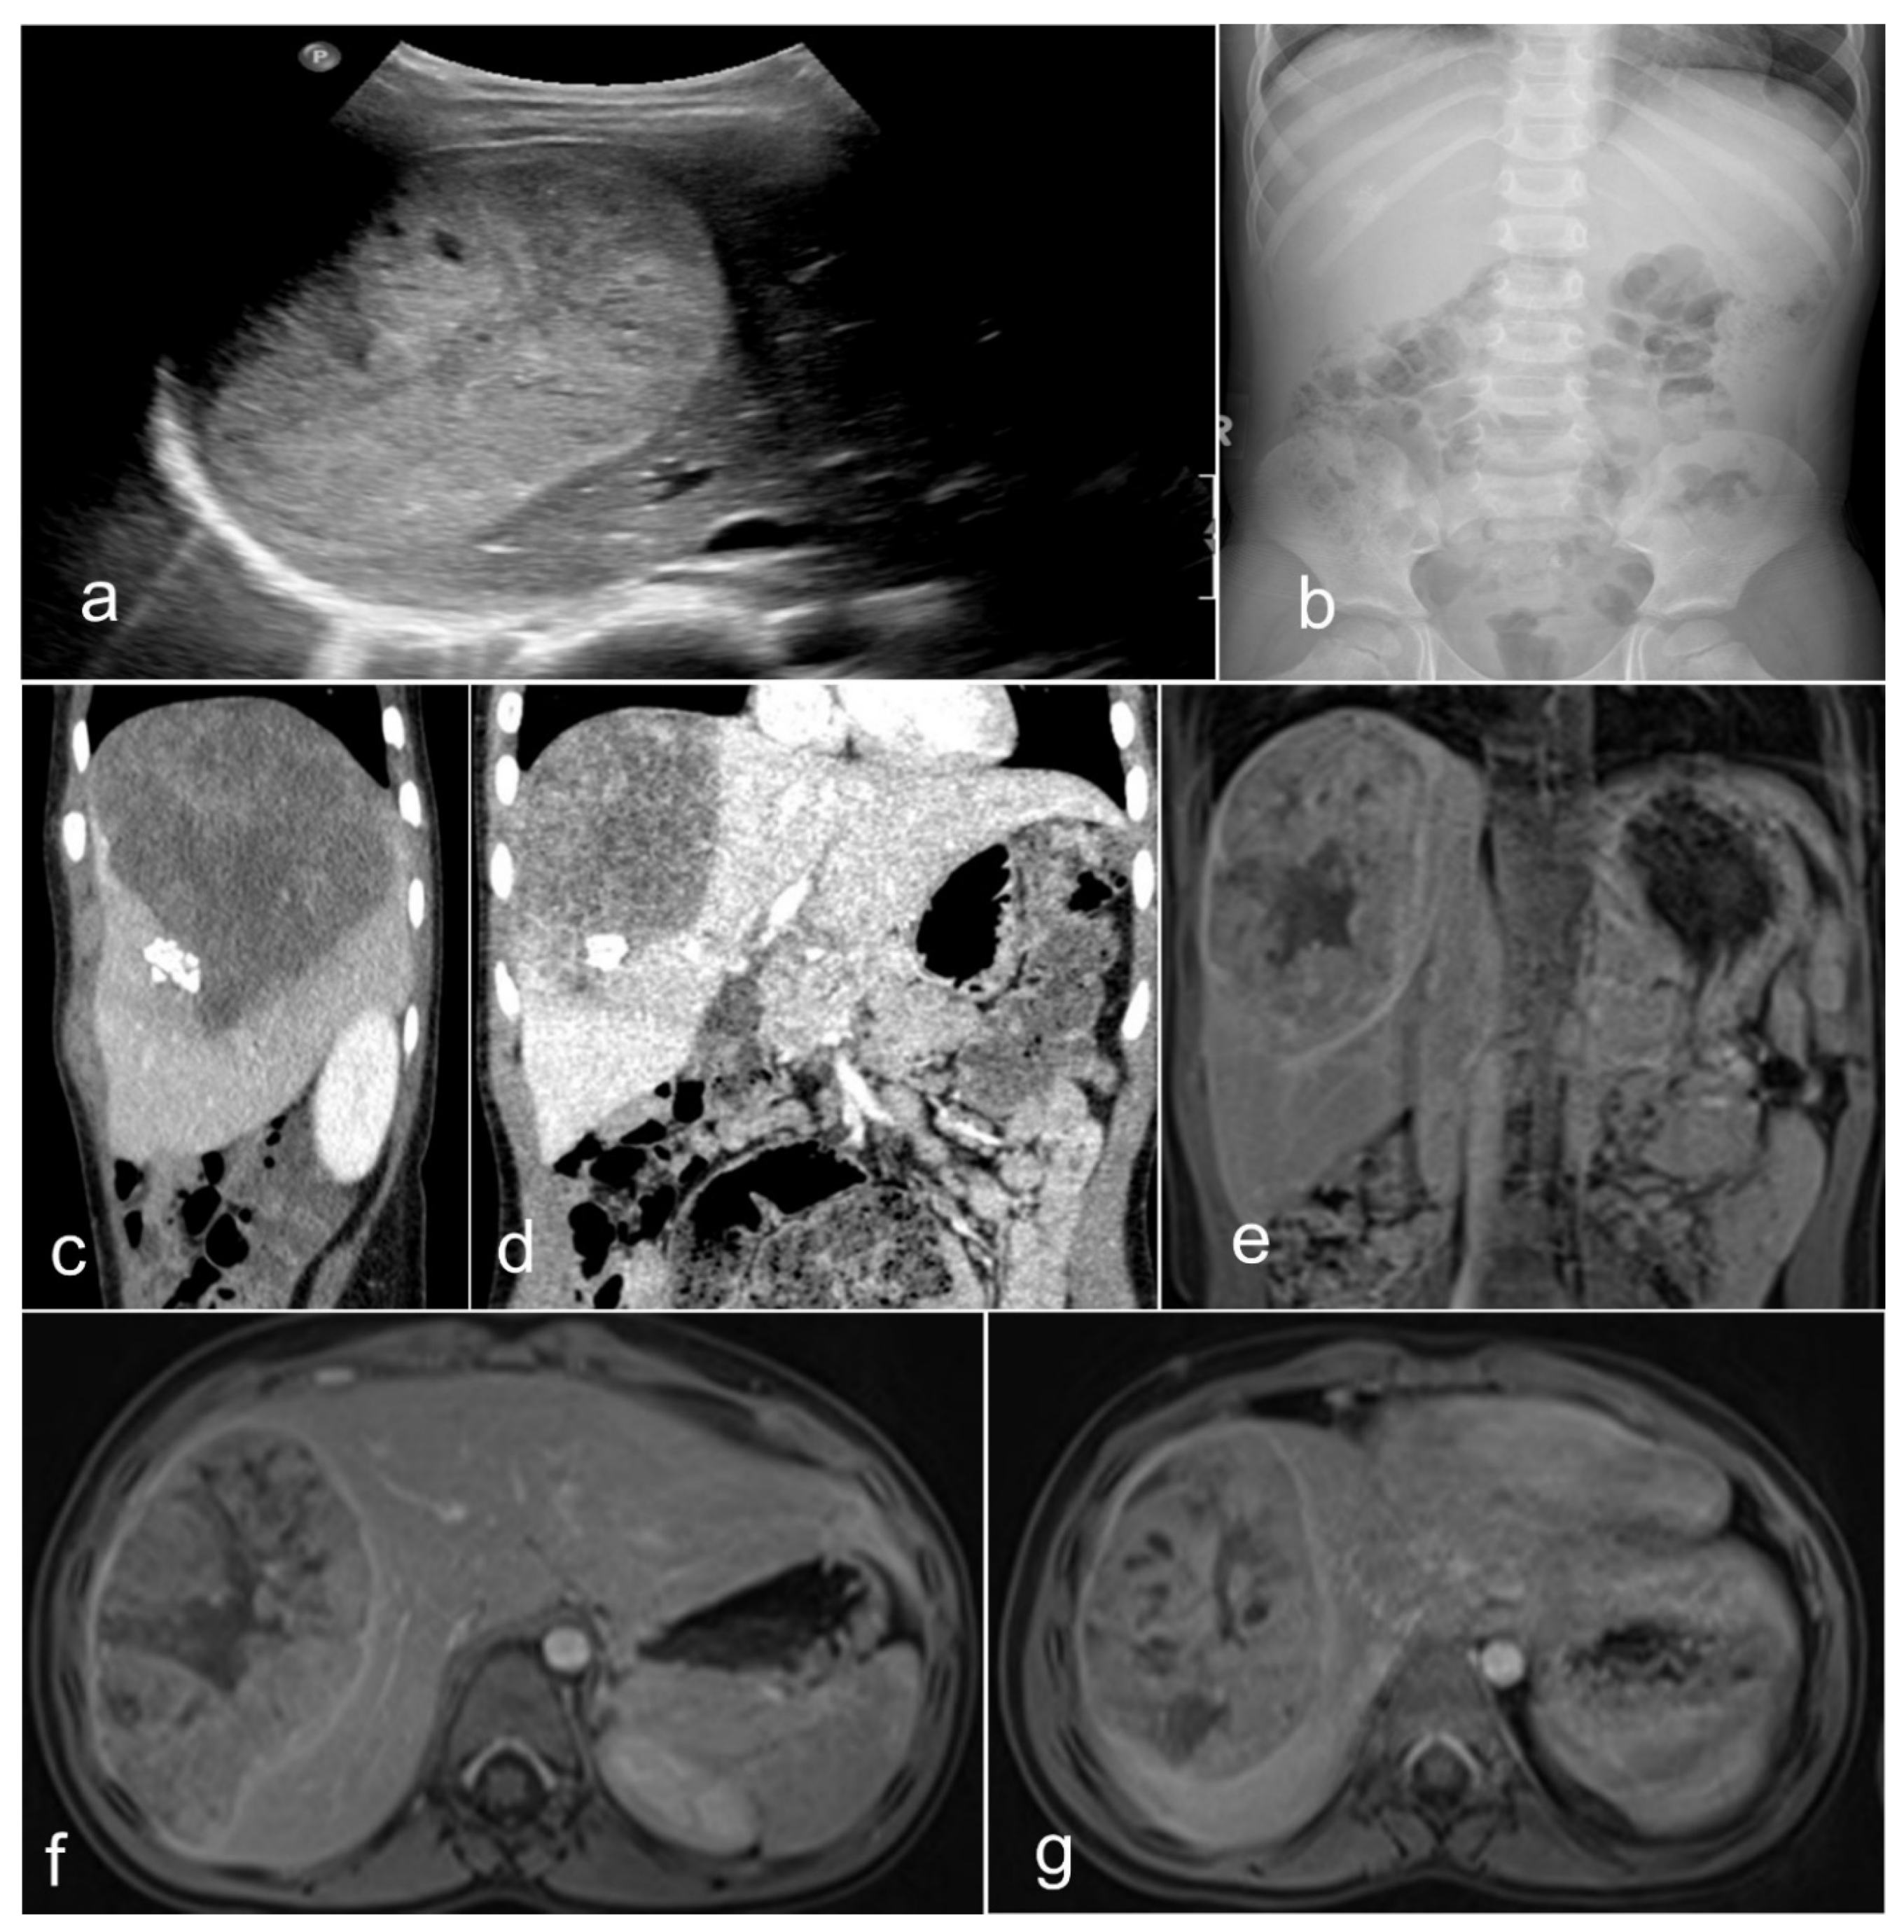

1.2. Clinical-Radiological Features